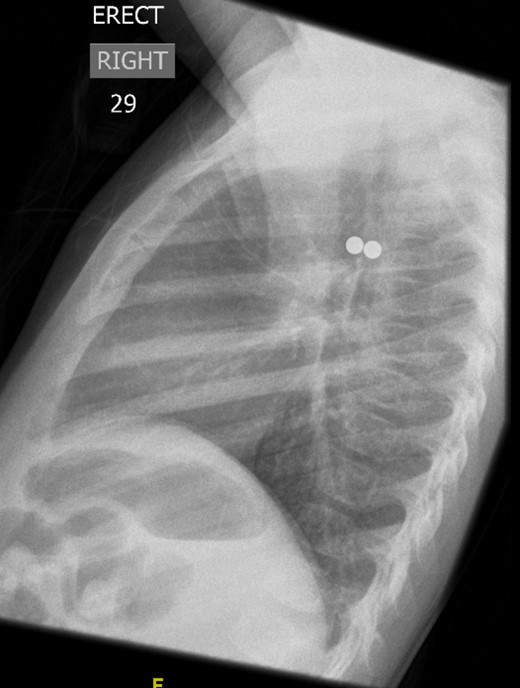

A 3-year-old girl was referred to the asthma clinic with a 3-month history of morning cough and wheeze. She was seen multiple times by her general practitioner (GP) who initially diagnosed her with upper respiratory tract infection. Her symptoms persisted despite salbutamol inhaler treatment so the GP organised a chest x-ray (CXR) (Fig. 1). It was reported that the left lung was translucent with reduced peripheral lung markings: finding consistent with asthma with bronchial plugging or a post infective bronchiolitis. It also showed a round radio-opaque FB over the left main bronchus. However, this was labelled as ‘Clothing Artefact’ on the actual radiograph and therefore did not alarm the GP or the reporting radiologist. A repeated PA CXR (Fig. 2) was undertaken in the asthma clinic where all clothes and hair were removed from the thorax. This confirmed the presence of a metallic FB in the left main bronchus and the patient was immediately admitted for bronchoscopy and removal of the FB.

The repeated posterior–anterior CXR taken with all clothes and hair removed from the thorax of the patient. It confirmed the presence of a metallic foreign body in the left main bronchus.